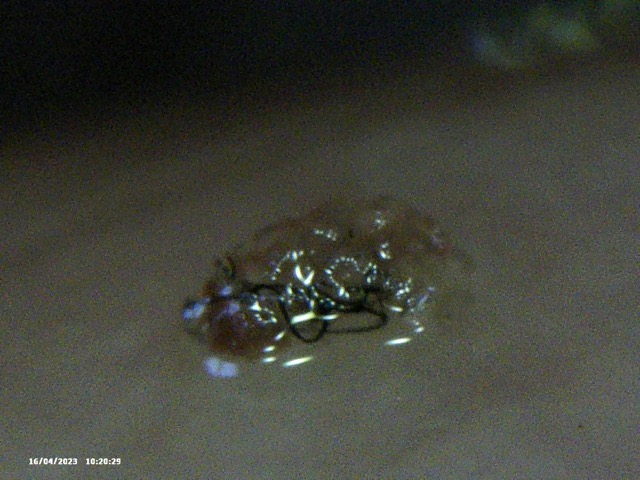

Below is the selection of recent images that I showed him. In isolation they look like they could be ‘anything’ – but with the context of my described condition, and the consistency of objects being extracted, I thought this might, at a minimum be considered ‘not right’ and warrenting further investigation. Silly me.

Image Notes:

- That is my fingerprint in the background.

- All objects are recent and have been extracted over the last 2 weeks

- I simply cannot see some of these objects – however I can feel them, ROCK HARD.

- ‘Hair’ included for a sense of scale and also to help counter the lazy argument ‘That could be Hair embedded in those objects’ – mental gymnastics.

- This is a small selection of what I’m taking out of my skin where I am feeling movement, there are literally 100’s of these things. Imaging them become’s pointless as they are similar.

- Average Distance between fingerprint ridges is 0.15mm for a sense of scale.